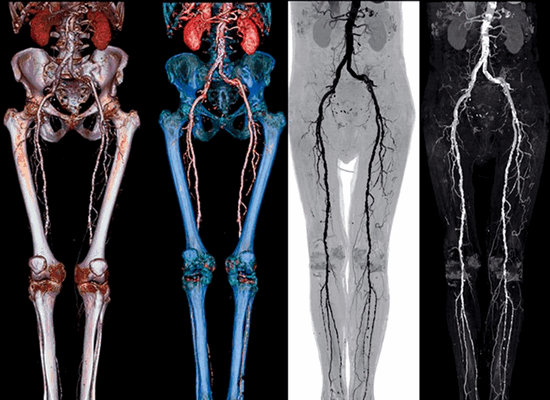

3D-реконструкция аорты - брюшной отдел и бифуркация

Компьютерная томография аорты и ее ветвей

Мультиспиральная компьютерная томография (МСКТ) аорты - это вид компьютерной томографии используемый для получения плоских и трехмерных изображений брюшной аорты и ее ветвей с помощью внутривенного введения контраста. Мультиспиральная компьютерная томография позволяет получить трехмерное изображение любого отдела аорты и ее висцеральных ветвей. Данное исследование прекрасно подходит для выявления аневризм аорты и висцеральных ветвей, атеросклеротических сужений и других заболеваний аорты.

В стандартный протокол КТ ангиографии брюшной аорты и ветвей входит обследование следующих структур:

общая печёночная артерия

левая желудочная артерия

общая печеночная артерия

верхняя брыжеечная артерия

нижняя брыжеечная артерия

общая подвздошная артерия

внутренняя подвздошная артерия

наружная подвздошная артерия

общая бедренная артерия

глубокая артерия бедра

поверхностная бедренная артерия

передняя большеберцовая артерия

задняя большеберцовая артерия

Что лучше: МРТ или КТ брюшной аорты?